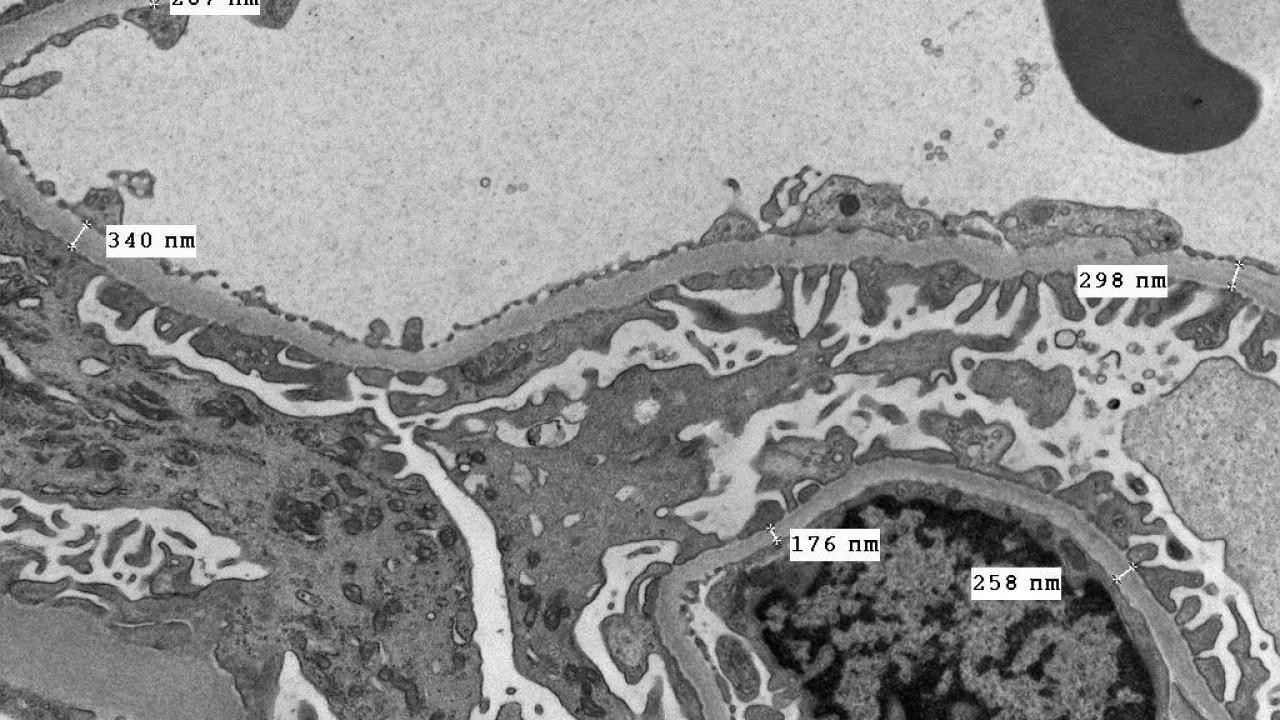

Kidney, Glomerular basement membrane with structural abnormalities